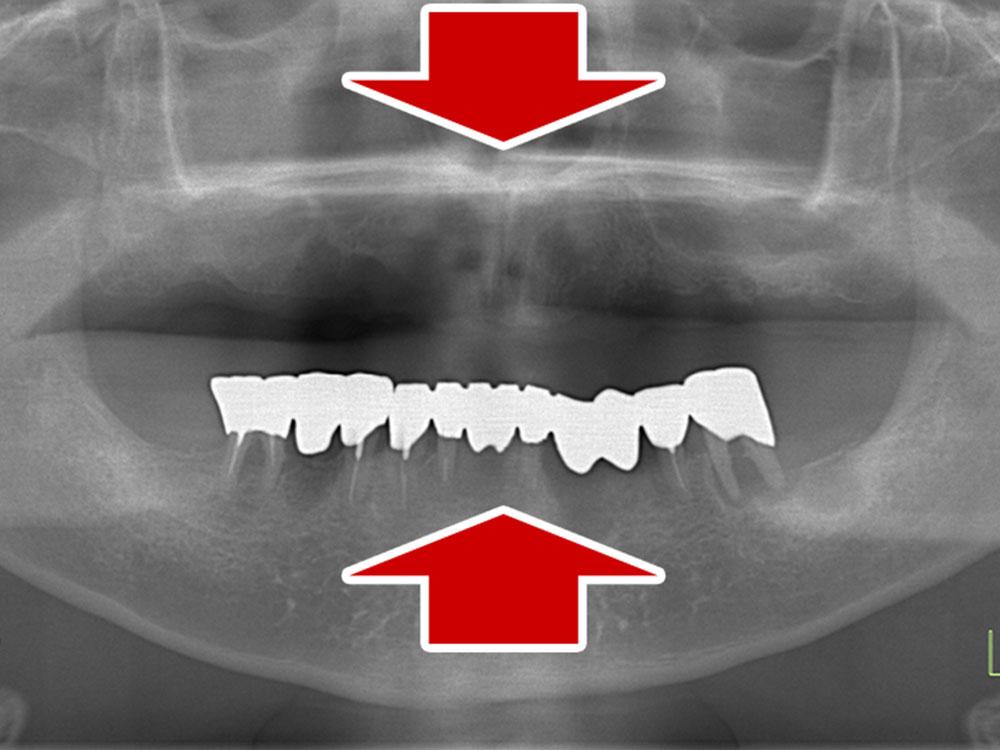

- 主訴

- 入れ歯が気持ち悪く、しっかりと食べれない。本当につらい。美味しく食べて、豊かな人生を過ごしたい。

- 処置内容

- 上顎6本(オールオン6)

- 治療費用

- 上顎350万円(税込)

- 治療期間

- 上顎1年(仮歯まで8か月)/約10回

- リスク

- 上部構造物、仮歯の破折、術後の腫れ(3日)、人工歯根脱落のリスクがあります